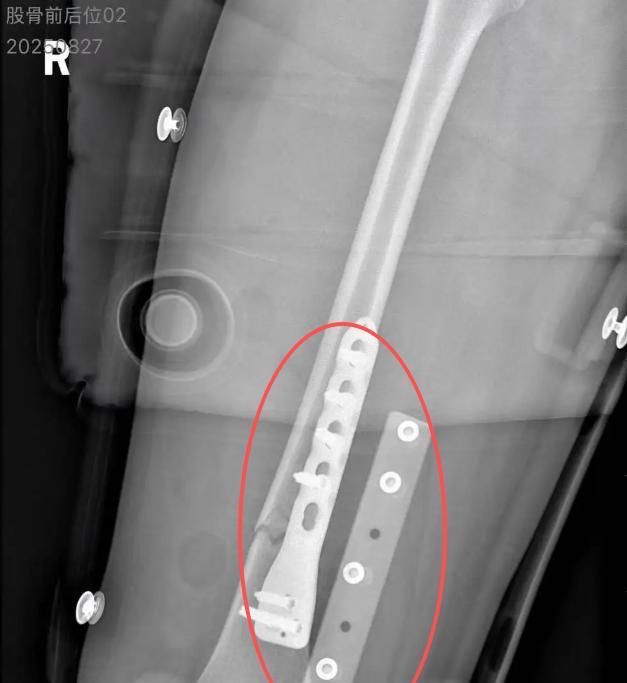

浙江,朱女士带10岁女儿坐火车去杭州,特意买下铺车票。凌晨一点左右,上铺男乘客拿眼镜时,因列车晃动跌落砸到朱女士女儿,致其右股骨骨折。男乘客起初陪去医院,垫付押金、买护理用品,后称回家筹钱便失联,朱女士多次联系无果,准备通过法律维权。 素材来源于:红星新闻 2025年8月24日这天,开往杭州方向的列车上,一场本应温馨的亲子游,因上铺乘客的跌落,演变成了一场责任与信任的拉锯战。 那夜,朱女士和女儿在下铺的床铺上,被一阵哭声惊醒,女儿的腿被砸得蜷缩成一团,上铺的男乘客站在床边,手里攥着眼镜,脸色煞白,解释声带着颤抖,他说列车晃动让他失了重心,从铺位跌落,砸中了孩子。 朱女士顾不上追问细节,赶紧联系如何把女儿以最快的方式送去救治,经检查,女儿的右腿被固定在支架上,右股骨骨折,得住院。 这时,男乘客出现了,他主动垫了住院押金,跑去买了护理垫、毛巾,甚至蹲在床边帮女儿调整枕头,朱女士看着他忙前忙后的样子,心想这人虽然闯了祸,但至少有担当,或许能一起扛过这道坎。 可第二天,男乘客的承诺就变了味,他说钱不够,得回家筹,朱女士看着女儿疼得直抽气的脸,又想着人家已经垫了钱,便同意了,她安慰自己,或许人家家里真有难处,等筹到了钱就会回来。 然而,男乘客的电话从无人接听到直接关机,朱女士从最初的期待,到焦虑,再到绝望,她每天守在病房里,看着女儿因为疼痛睡不着觉,小脸都瘦得脱了形。 她开始打听男乘客的消息,问当时的列车员要联系方式,查医院缴费记录,托朋友发寻人启事,可所有努力都没有一点回音,她这才明白,那个主动帮忙的男乘客,早就把责任抛在了脑后。 朱女士的存款很快见了底,她不得不向亲戚朋友借钱,可借来的钱总是不够,女儿的治疗不能停,她想不通,为什么一个成年人的承诺,会这么轻易忘记。 最扎心的不是意外本身,而是责任与信任的断裂,男乘客跌落砸人,是意外,但事后失联,就是逃避,他或许觉得,垫了押金、买了东西,就已经尽了义务,可对于一个10岁的孩子来说,这些只是最基础的弥补,远不足以抵消她承受的痛苦。 更讽刺的是,有人同情朱女士,觉得她太不容易,也有人指责她太软弱,不该轻易放男乘客走,可真正该被讨论的,是如何让责任不因逃避而消失,如何让信任不因失联而崩塌。 列车作为公共交通工具,乘客的安全本就该是首要考量,设计是否合理,列车晃动时是否有提醒,这些细节都可能成为意外的起因。 从法律角度,男乘客行为该如何定性,又将面临怎样的处罚呢? 男乘客在列车上,因列车晃动失了重心从铺位跌落砸中孩子,这一行为造成了孩子右股骨骨折的严重后果。 《民法典》规定,行为人因过错侵害他人民事权益造成损害的,应当承担侵权责任。 列车晃动虽是外部因素,但男乘客作为完全民事行为能力人,应当预见到在列车行驶过程中可能出现的晃动情况,却没有尽到合理的注意义务,导致自己跌落砸伤孩子,主观上存在疏忽大意的过失。 男乘客从铺位跌落砸中孩子,这一行为直接造成了孩子右股骨骨折的损害结果,且侵害行为与损害结果之间存在因果关系。 基于以上分析,男乘客构成了侵权行为。他应当承担的民事责任包括赔偿医疗费、护理费、交通费、营养费、住院伙食补助费等为治疗和康复支出的合理费用,以及因误工减少的收入。 男乘客失联逃避责任的行为,会受到什么样的处罚? 在承担侵权责任过程中,男乘客起初主动垫付部分费用,但后续却以筹钱为由离开,之后电话无人接听直至关机,完全失联,拒绝继续承担应尽的赔偿责任。 民事主体从事民事活动,应当遵循诚信原则,秉持诚实,恪守承诺。 男乘客在造成孩子受伤后,有义务积极承担赔偿责任,而他却通过失联的方式逃避,这是对法律义务和道德责任的公然违背。 从民事角度,朱女士可以通过法律途径维护自身权益。她可以提起诉讼,要求男乘客继续履行赔偿责任。 从法律层面看,男乘客的行为已涉嫌侵权,他因自身过失导致他人受伤,理应承担医疗费、护理费等赔偿责任,失联不是逃避的借口,法律会追着他到天涯海角,朱女士选择起诉,是正确的选择,也是对失信者最有力的反击。 责任不是一句道歉就能解决的,信任不是一次帮忙就能建立的,在公共场合,每个人都该对自己的行为负责。 在意外发生后,更该直面问题,而不是选择逃避,毕竟,孩子的哭声不会因为失联而停止,法律的审判也不会因为逃避而缺席。 朱女士现在每天守在女儿病床前,一边照顾她,一边准备诉讼材料,她希望,等女儿好了,还能带她去看杭州的西湖,只是这一次,她会更加小心,因为有些教训,一次就够了。